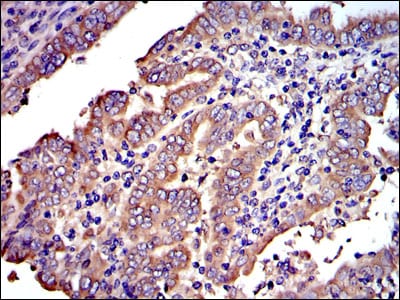

分类: 科研抗体货号: 30259别名: PBT; SCFR; C-Kit; CD117应用: WB,IHC反应种属: Human